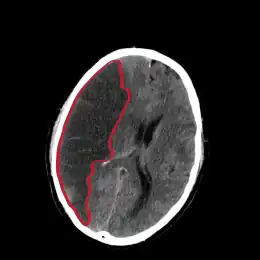

L’infarctus cérébral, appelé aussi accident ischémique cérébral, est un type d'accident vasculaire cérébral. C'est un déficit neurologique soudain d'origine vasculaire causé par un infarctus au niveau du cerveau.

L'infarctus cérébral est causé par une diminution voire un arrêt brutal du débit sanguin dans les branches du réseau vasculaire alimenté par un vaisseau (en général une artère) subissant un blocage partiel ou total (par thrombose, embolie, sténose, ou autre cause pas toujours identifiable).

Ainsi, les cellules nerveuses alimentées par ces branches sont privées soudainement d'oxygène et de sucres, ce qui provoque en quelques minutes leur détérioration ou leur mort.